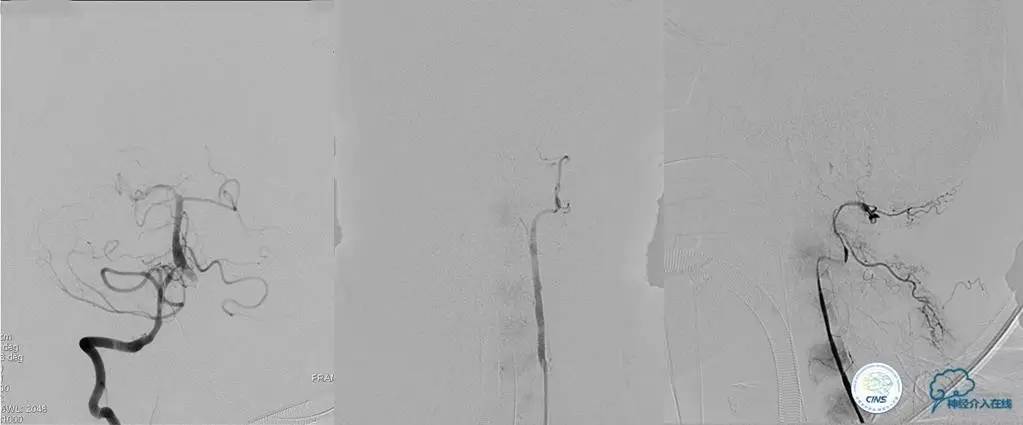

术前DSA

▼2013-12-13

▼2013-12-27

术后仍残余部分狭窄,但头晕明显缓解。

术后3个月复查时予行支架内球囊扩张,狭窄改善。